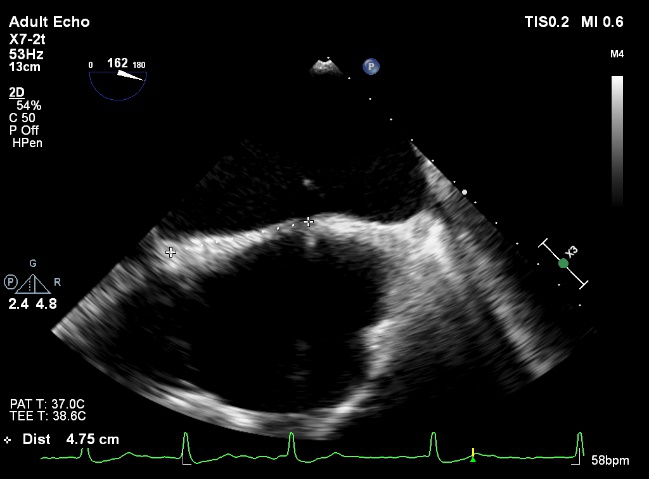

CT提示为该患者三叶瓣,右无轻度融合,冠脉开口高度尚可,窦部空间可,髂总动脉近环形钙化,内径可,计划予以23mm球囊扩张,植入Venus A 26瓣膜。

CAG:LAD近中段弥漫钙化,近段80%狭窄,中段90%狭窄,D190%狭窄,中间支近段90%狭窄,右冠近中段弥漫病变,最重狭窄50%。考虑患者胸痛症状可能为冠心病+AS共同作用,以及患者冠脉病变钙化严重,予以旋磨+PCI+TAVR一站式处理。